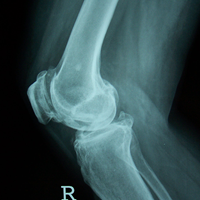

Case:1 TKR

Pre-Op Lateral